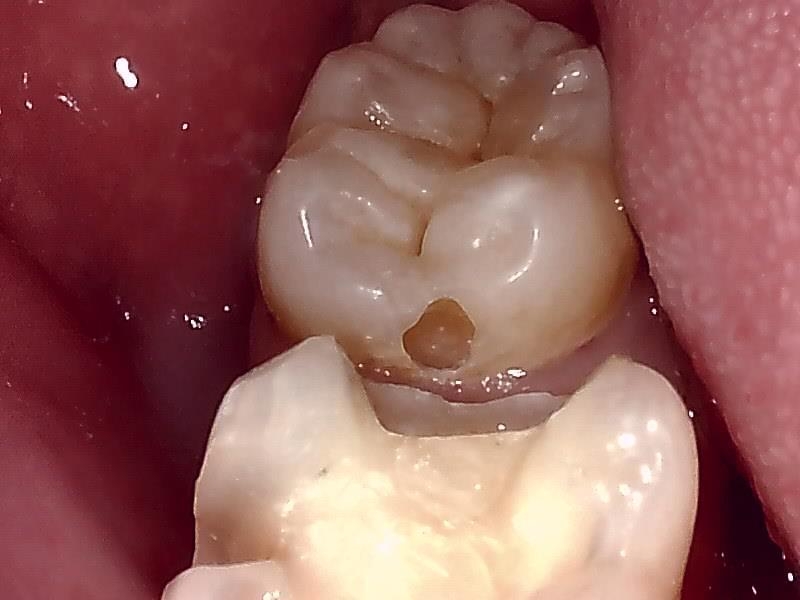

写真; セラミックインレー装着後の歯冠の仕上がり(咬合面観)